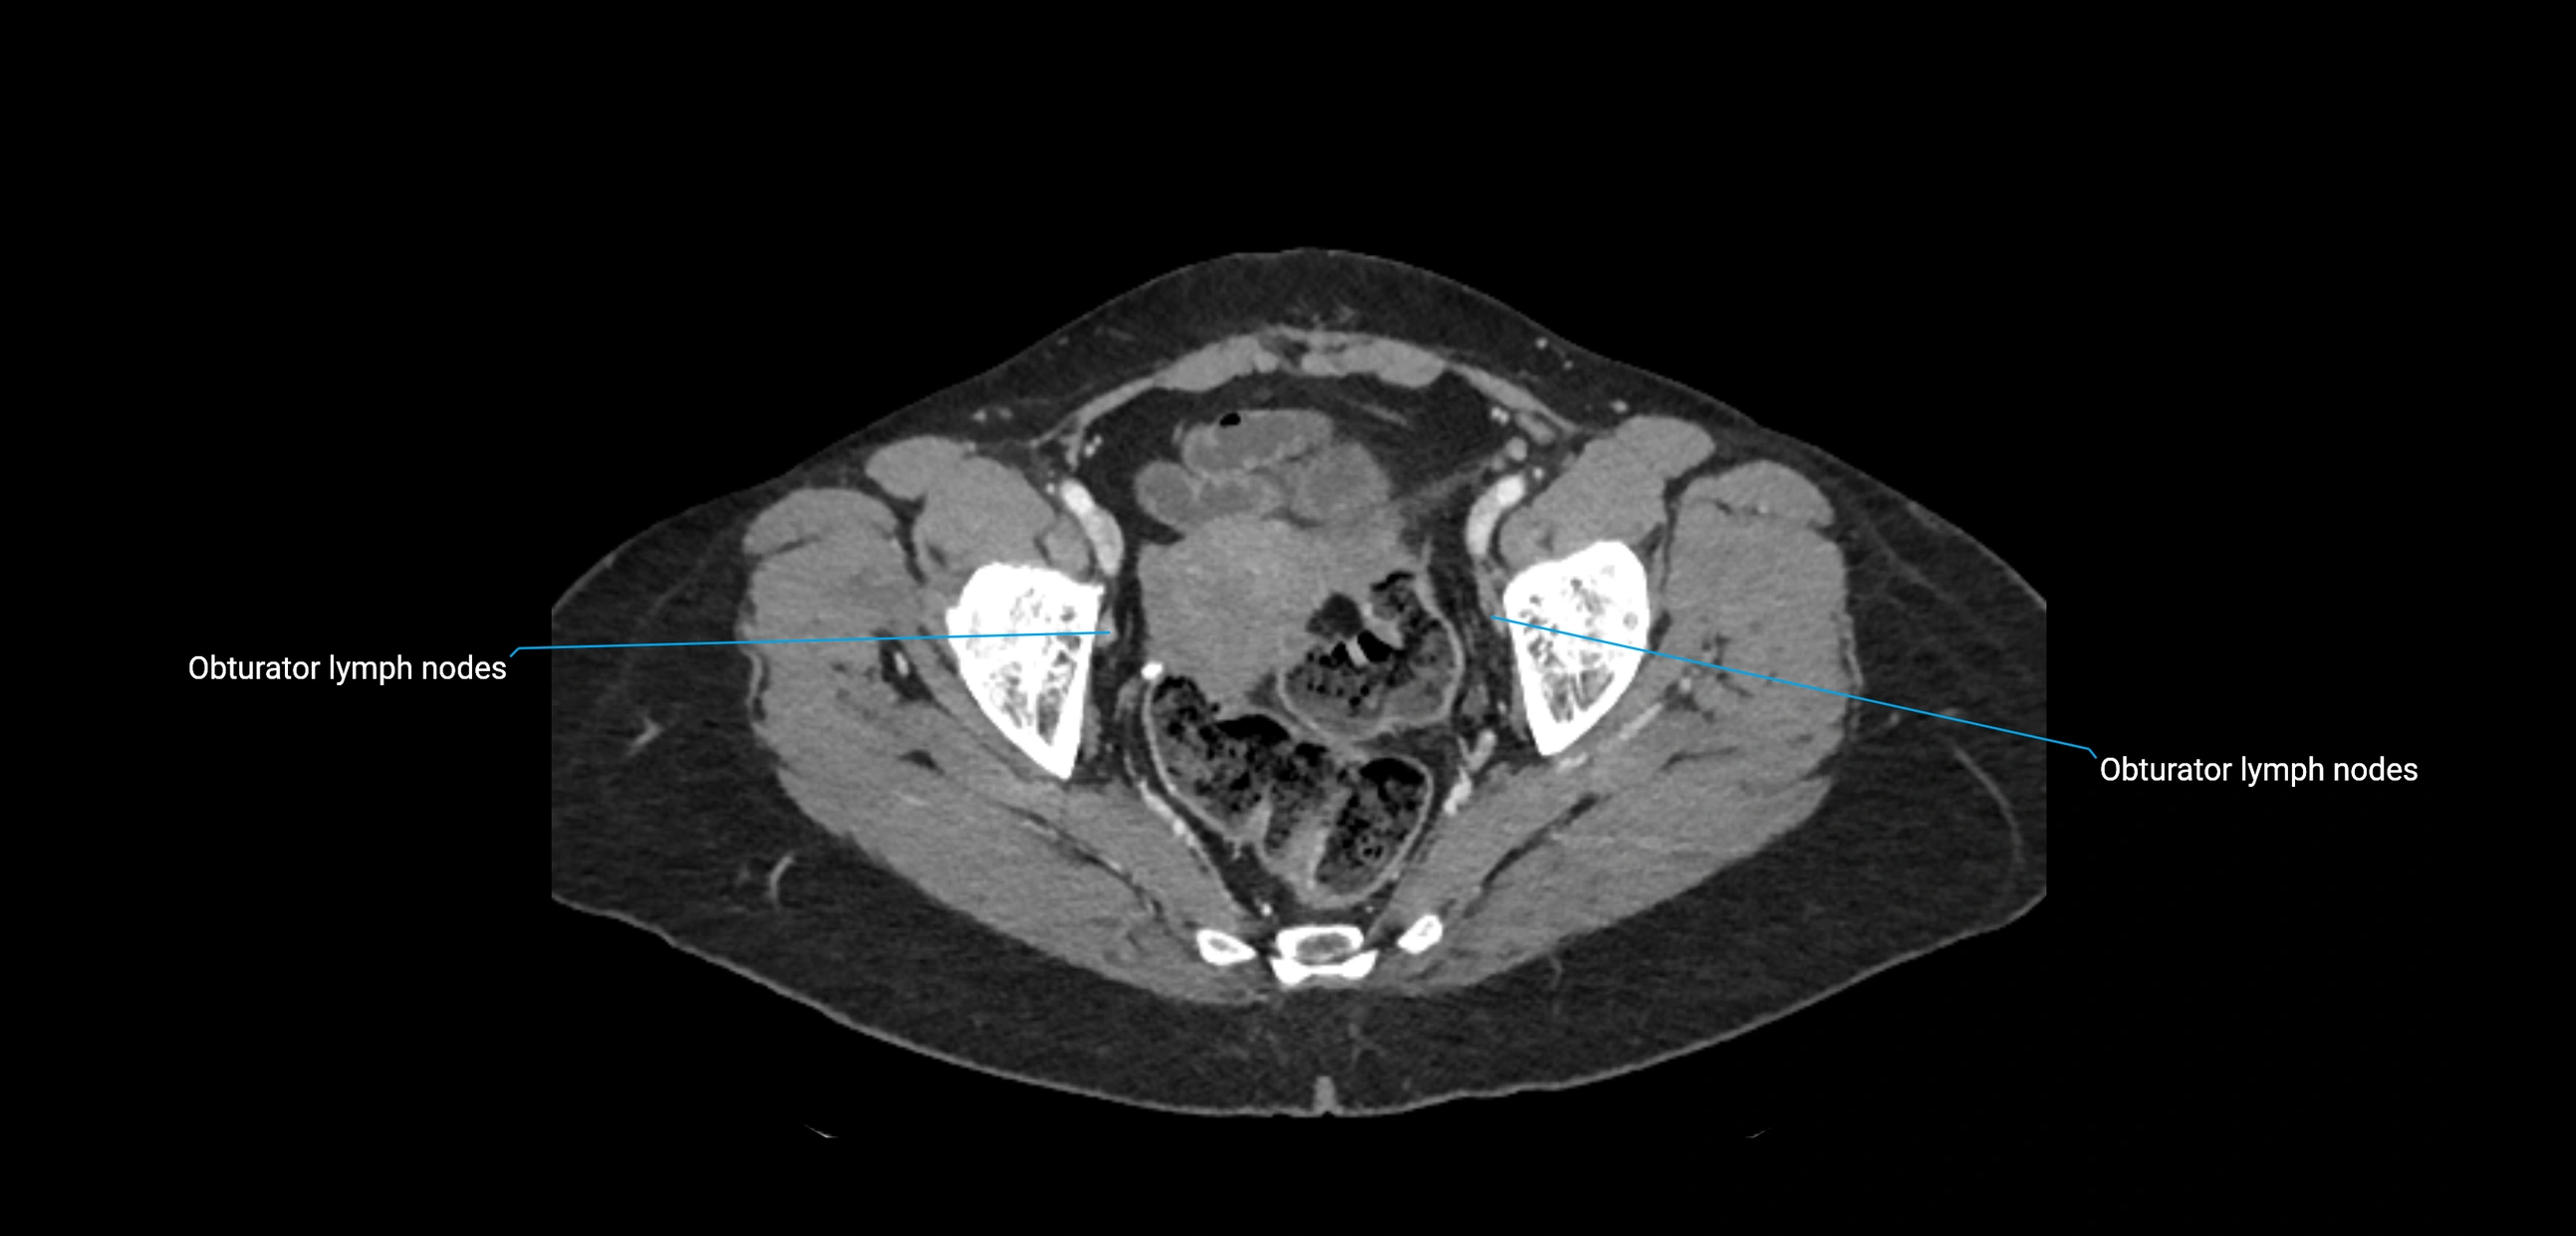

CT Appearance

CT Pre-Contrast:

• Nodes appear as soft-tissue density nodules adjacent to the aorta and IVC

• Calcification may be seen in chronic infections (e.g., tuberculosis)

CT Post-Contrast:

• Normal nodes enhance homogeneously

• Malignant nodes may show heterogeneous enhancement, central necrosis, or conglomerate formation

• Size >1 cm short axis is suspicious, though morphology and distribution are equally important

CT image

image